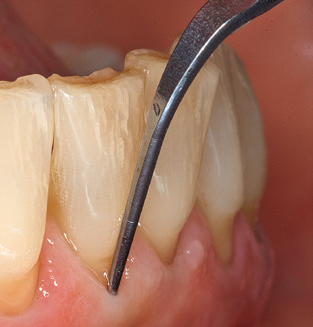

Abb. 4: Für das Sondieren an dentalen Implantaten sind biegsame, millimeterskalierte Sonden empfehlenswert (z.B. Colorvue Kit PCV11KIT6, Hu-Friedy). – Abb. 5a und b: Eine gerade Arbeitsspitze (1P, W&H Dentalwerk Bürmoos GmbH) ist universell für die Instrumentierung natürlicher Zähne geeignet. – Abb. 6: Für die Bearbeitung schwer zugänglicher Bereiche der Zahn- und Wurzeloberflächen (z.B. Furkationen) bieten sich gebogene Arbeitsspitzen (3Pr/3Pl, W&H Dentalwerk Bürmoos GmbH) an. – Abb. 7: Die spitz zulaufende sechseckige Implantatreinigungsspitze (1I, W&H Dentalwerk Bürmoos GmbH) ermöglicht eine atraumatische und effiziente Reinigung der Kronen- und Abutmentoberflächen. – Abb. 8: Für die manuelle Instrumentierung der Implantatoberflächen sind Titan- oder Carbonküretten geeignet.

Die gute Ausleuchtung des Arbeitsfeldes stellt eine wesentliche Erleichterung dar. Bei dem von den Autoren genutzten System ist dies gelungen, indem ein 5­facher LED­Ring in das Handstück integriert wurde. Natürlich werden für dieses System unterschiedliche Arbeitsspitzen für die jeweiligen Indikationsbereiche angeboten. Eine gerade, universell einsetzbare Spitze ist das Basisinstrument zur maschinellen Instrumentierung natürlicher Zähne (Abb. 5a und b). Für schwer zugängliche Bereiche im Seitenzahnbereich werden gebogene Spitzen angeboten, die auch einen Zugang zu freiliegenden Furkationen ermöglichen (Abb. 6).